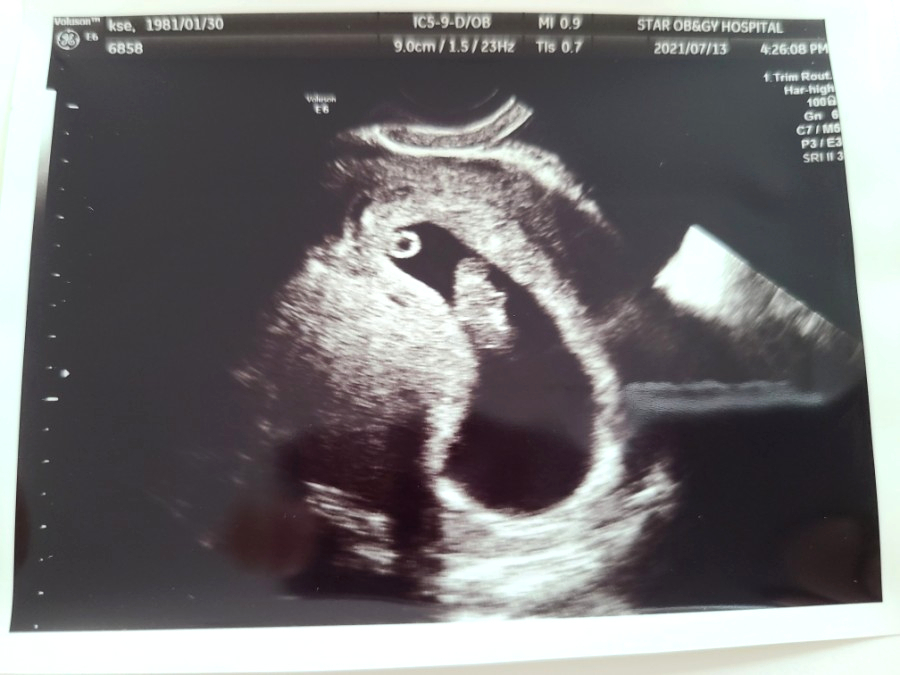

아무튼 7월 13일을 기준으로 전 8주 차가 되었다고 하셨고 이날 처음으로 아기의 심장박동을 확인할 수 있었어요.

심장소리를 들으니 진짜 괜히 뭉클해지더라고요. '내 배속에 정말 생명이 있구나!'란 사실이 그제야 실감 난 것 같아요.

아기의 크기는 1.67CM. 이날 아기의 얼굴과 몸도 초음파로 볼 수 있었어요.